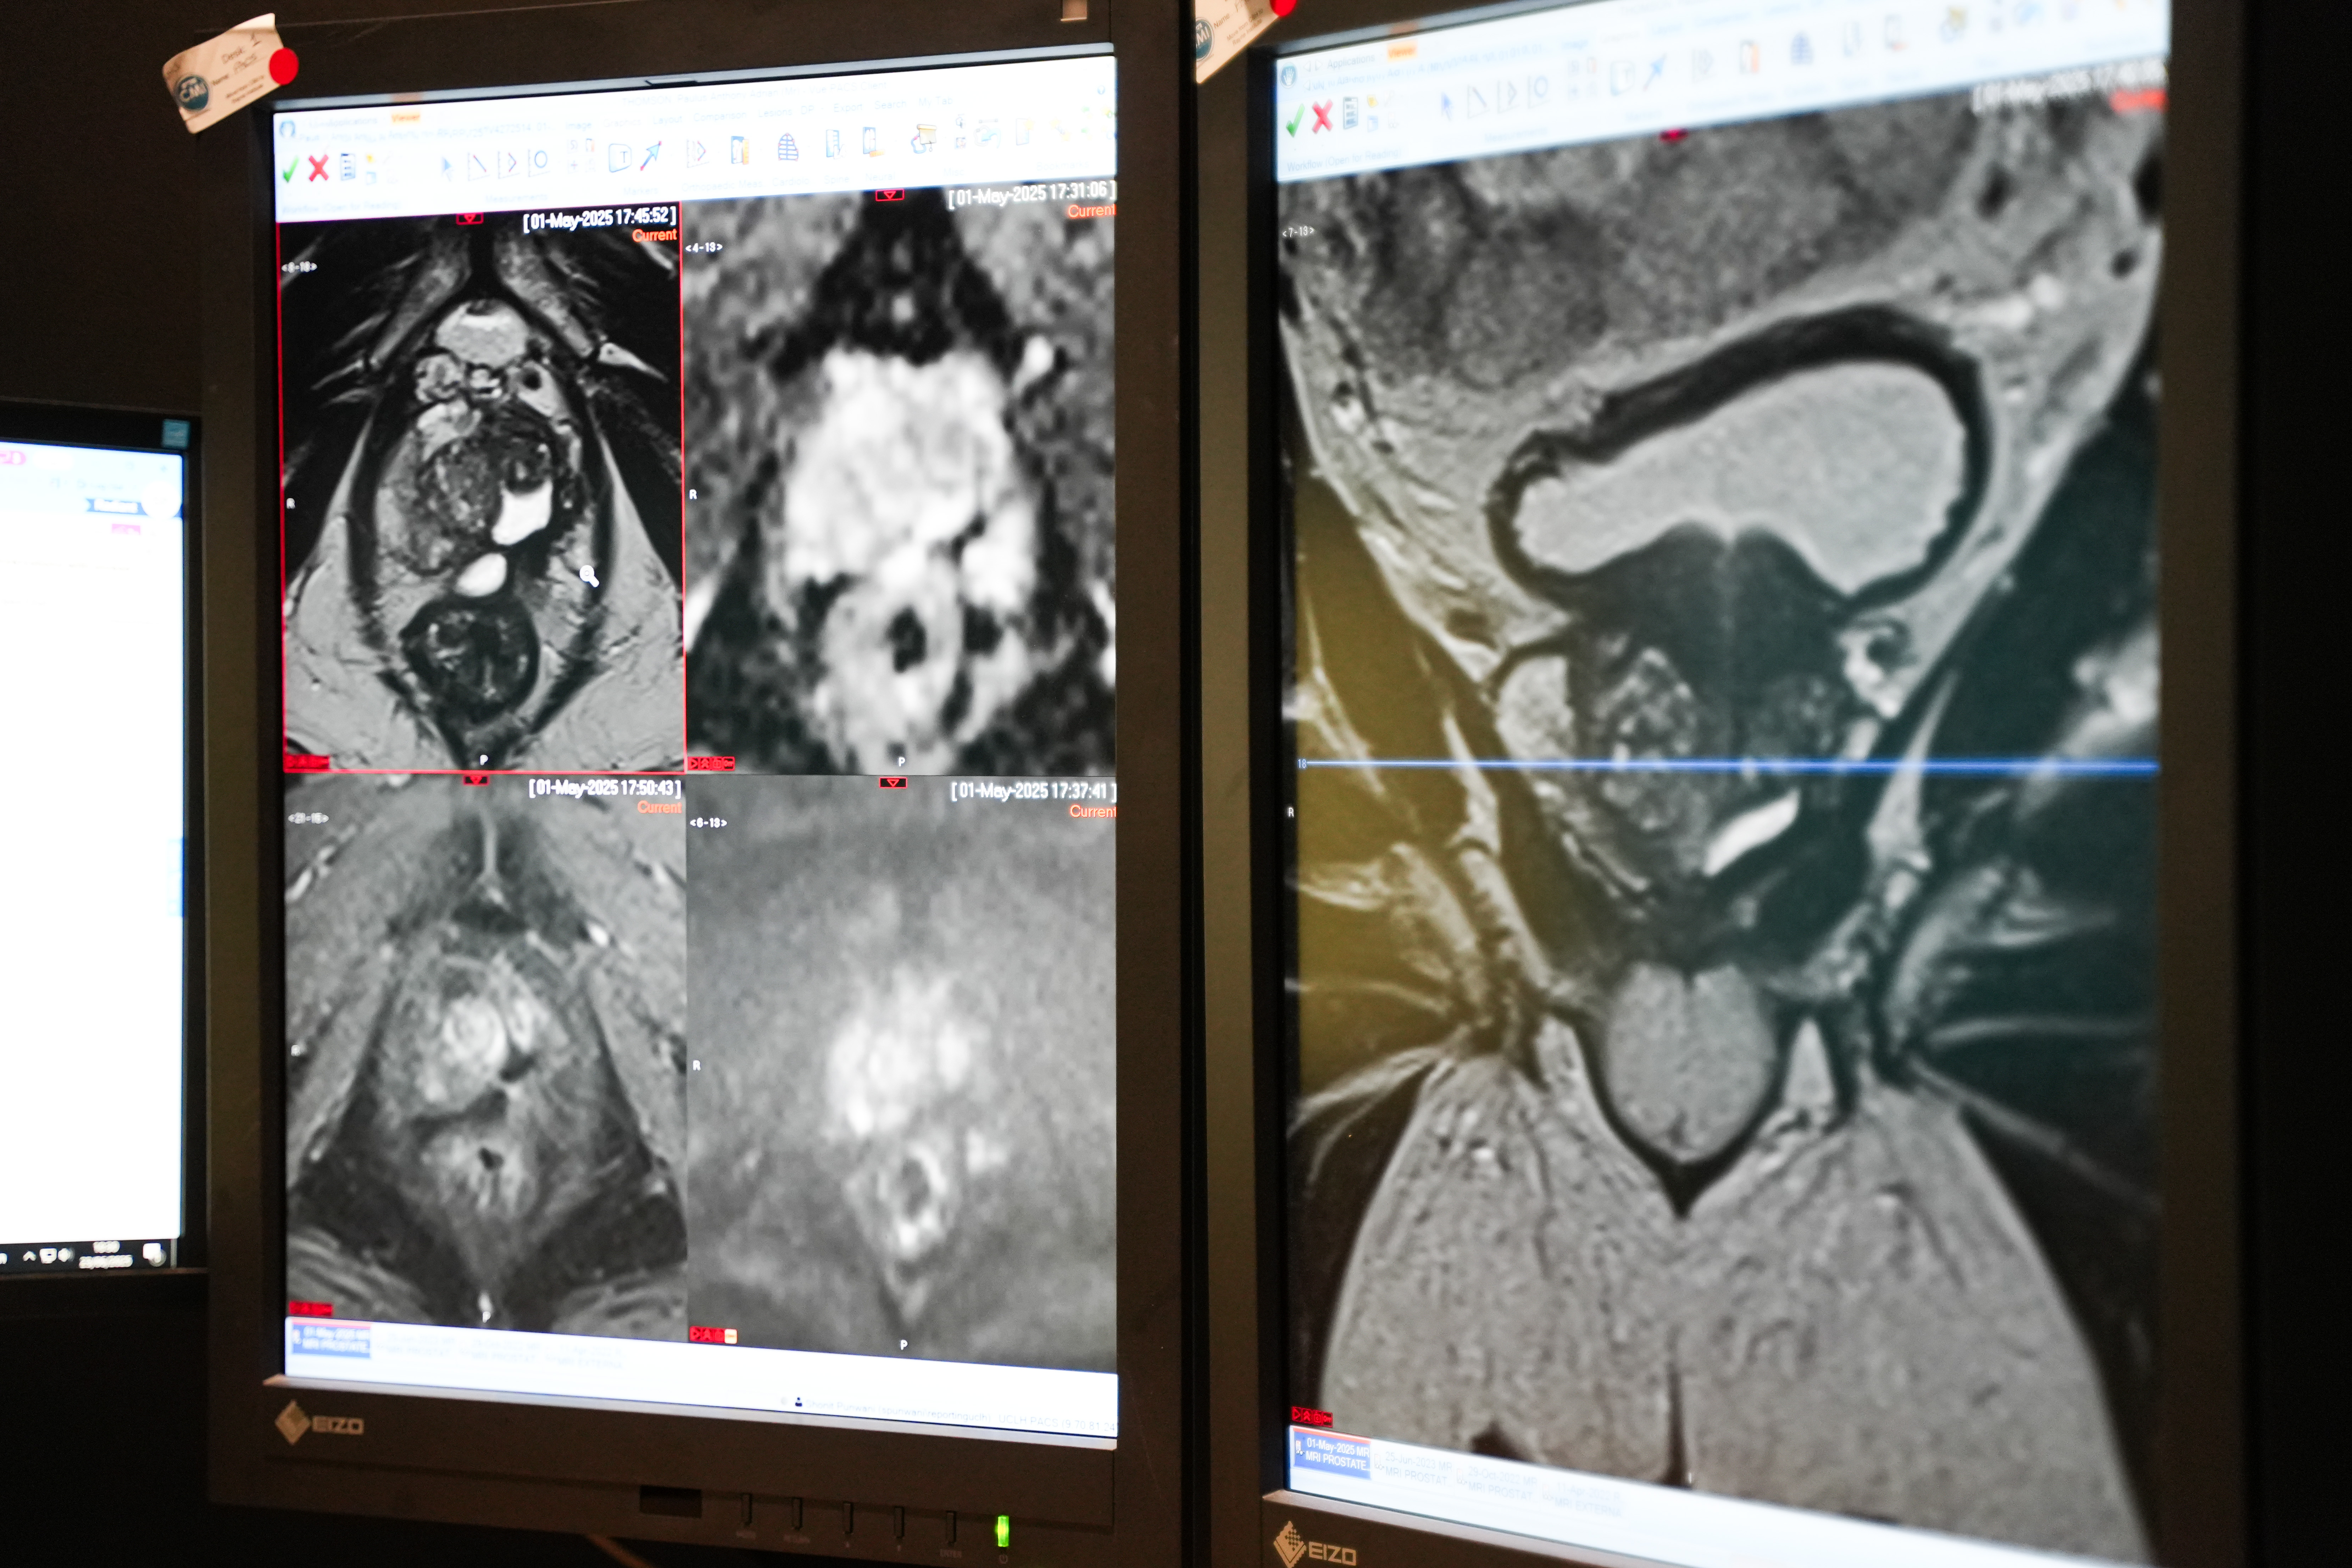

In stage one, involving around 13,500 men, researchers will compare four potential screening options, including fast MRI scans, genetic testing to identify men at high risk of prostate cancer, and PSA blood testing. A fast MRI is a 12-minute version of the full scan that uses magnetic resonance imaging (MRI) to produce a detailed picture of the prostate.